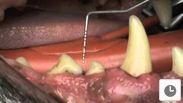

Dog With Severe Periodontitis

A dog with severe periodontitis is examined by Andrew Perry BVSc MRCVS on our YouTube channel.

video clip of dental examination

View video clip of the examination